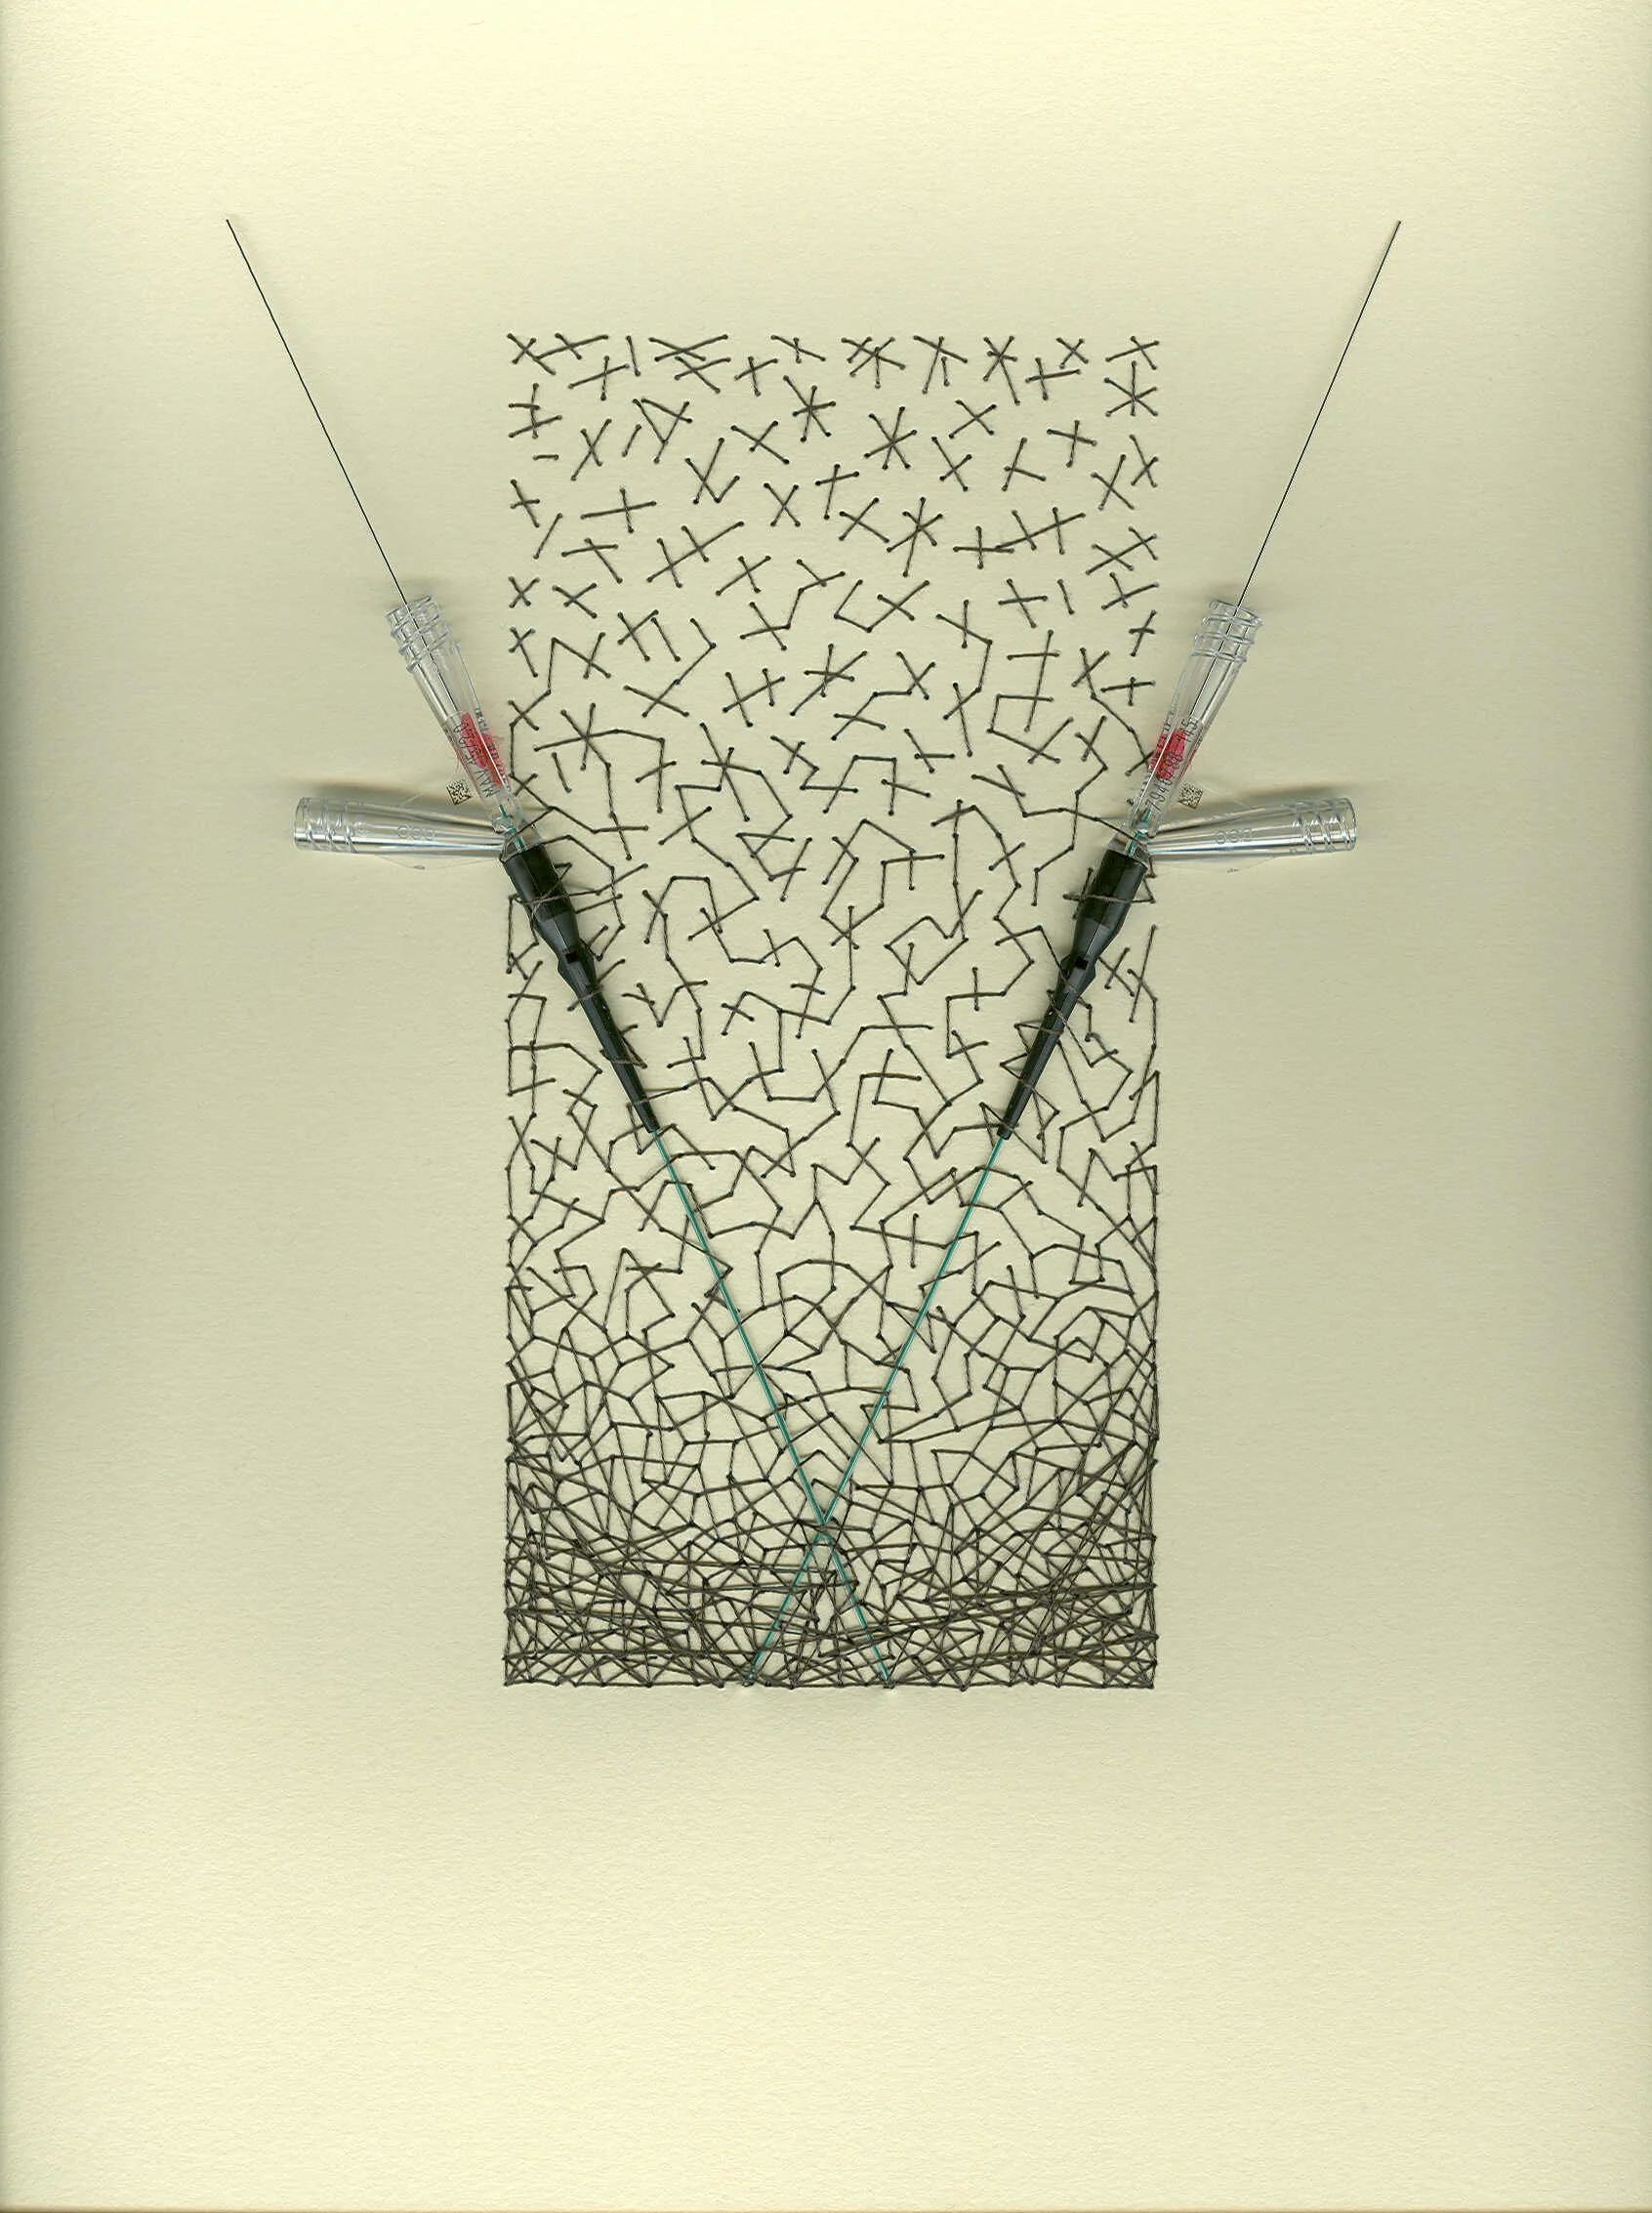

I’ve also had the pleasure of creating artwork for another corporate headquarter building based in MN. Boston Scientific commissioned me to create found object works that featured products which they created. You’ll see below some of those that feature angioplasty ports and balloons.

Chaos 2